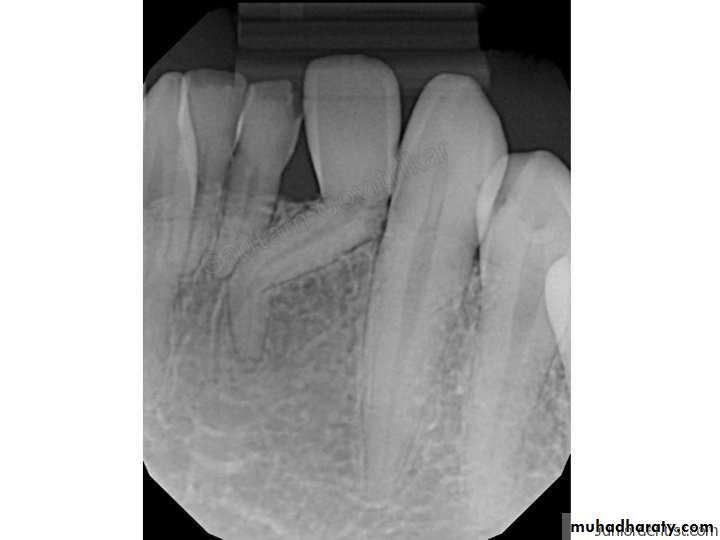

4. Dilacerated tooth

ReasonTrauma affecting the tooth bud during root formation